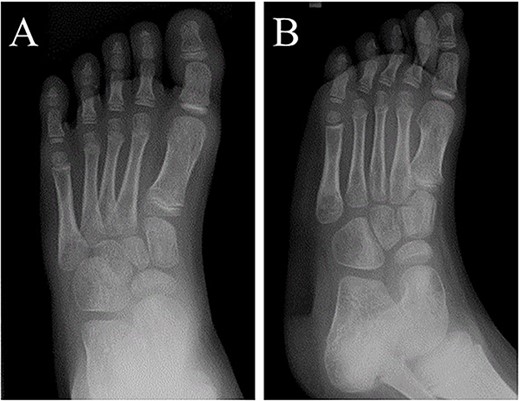

A 21-month-old Japanese female infant presented with a swollen mass on the dorsolateral aspect of the left foot. Her parents noticed the mass and brought the patient to our hospital. The patient had no past medical histories or complications prior to the occurrence. In addition, she received the BCG vaccine at the age of 4 months in Japan. At first visit to our hospital, physical examination revealed the ~3 × 3 cm mass was located on the dorsolateral aspect of the left foot and was hard accompanied by local heat (Fig. 1). Plain radiographs of the left foot showed a lytic lesion without periosteal reaction in the fifth metatarsal bone (Fig. 2). Magnetic resonance imaging (MRI) showed an isointense lesion on T1-weighted images and a hyperintense lesion on T2-weighted images around and within fifth metatarsal (Fig. 3). Gallium scintigraphy revealed intense uptake in the patient’s left foot (Fig. 4). In addition, laboratory examination was within normal. Based on medical history, clinical and imaging findings, we considered the possibility of neoplasia or osteomyelitis and performed an open debridement and biopsy of the lesion to make a diagnosis. The lesion was yellow and consisted of weak, adipose-like tissue that surrounded and continued into the inferior of the fifth metatarsal bone (Fig. 5). The lesion inside and outside the bone was resected as much as possible. Histopathologic examination of the lesion showed granulomatous inflammation including anaplastic giant cells, Langerhans-type giant cells and caseous necrosis (Fig. 6). Based on these results, TB or BCG osteomyelitis was considered as a diagnosis. The tuberculin test was positive, but the QuantiFERON TB test was negative. In addition, samples analyzed using polymerase chain reaction did not identify M. tuberculosis, but did identify the BCG Tokyo-172 strain. Per these findings, the patient was diagnosed with BCG osteomyelitis of the fifth metatarsal and oral treatment with anti-TB medicine including isoniazid (100 mg/day) and rifampicin (150 mg/day) was started. Clinical findings included reduction in swelling of the mass and gradual remodeling of the lytic lesion of the fifth metatarsal on plain radiographs (Fig. 7). However, 10 months after starting the anti-TB treatment, the mass recurred, and MRI revealed a residual high-intensity lesion around and inside the fifth metatarsal on T2-weighted fat-suppressed images (Fig. 8). It was determined that the lesion was difficult to control with anti-TB treatment alone, so an open debridement for the lesion was performed again. Histopathologic examination of the lesion revealed an epithelioid granuloma with necrosis. Therefore, the anti-TB treatment was continued. Six months after the second surgery, clinical and radiographic image findings showed complete improvement (Fig. 9). As a result, anti-TB treatment was ended. At the time of writing this report, 8 years after starting anti-TB treatment, there has been no recurrence.

Plain radiographs of the left foot showed the lytic lesion of the fifth metatarsal was remodeled gradually in (A) anteroposterior and (B) oblique views.